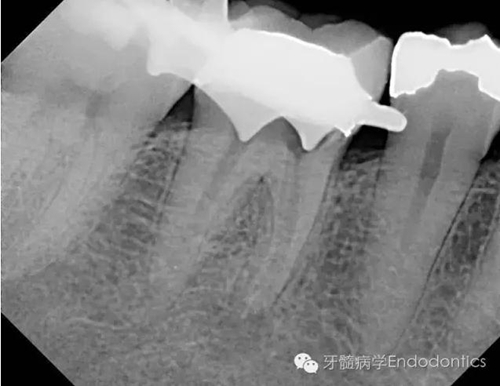

我決定對(duì)患牙行一次性根管再治療。我成功的取出了一根斷針和三根(其中兩根超出根尖)Thermofil(固核載體)。對(duì)所有根管進(jìn)行徹底的清理、成形,干燥后使用熱牙膠垂直加壓技術(shù)完成充填。

圖3.取出的斷針和固核載體